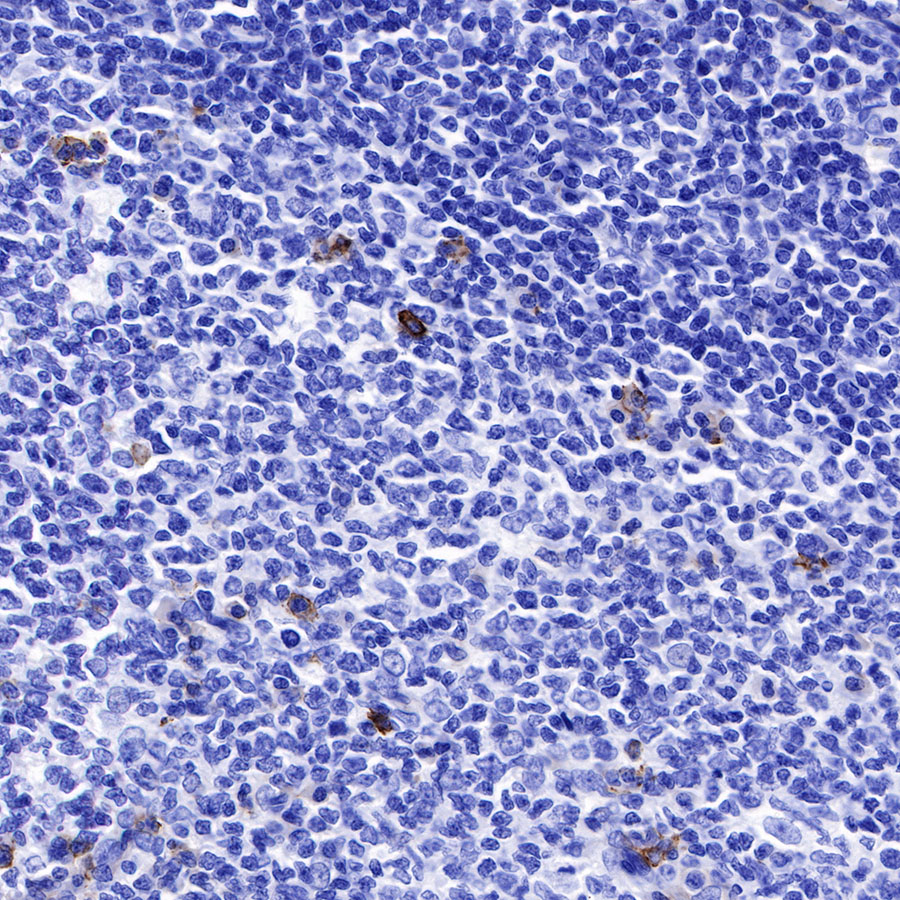

Immunohistochemistry

Immunocytochemistry